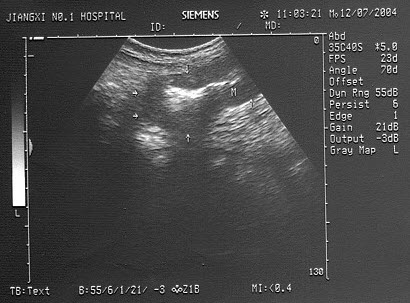

3、单项选择题

男,49岁,上腹不适1个月余。结合超声声像图,诊断为()

A.肝血管瘤

B.肝癌

C.局限性脂肪肝

D.肝脓肿

E.肝囊肿